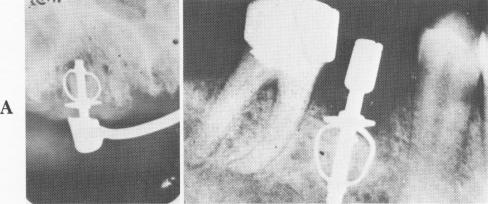

Fig. 5-15. Little bone regrowth is seen here because soft tissues have replaced bone in the band and around the post itself. (From Chercheve, R.: Implants endo-osseux, Paris, 1962, Labrairie Maloine.)

In addition to the cautious operative procedure necessary to create the walls of the slit, the implantologist must take great care to create a slit deep enough to set the bands well into bone. Bone can, and should, condense around the band (Fig. 5-14). This is frequently a problem. Because the post necessitates having deep alveolar bone, the implant may not be used in numerous sites because of danger to vital anatomic landmarks. Also, because the band leaves a large "empty" area within it, the danger of soft tissue invagination is great (Fig. 5-15) .